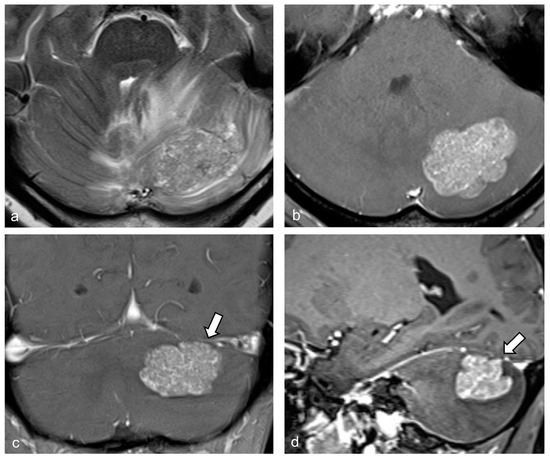

| Serrate sign | 18 (75.0) | 0 (0) | <0.001 |

| Branch-like enhancement | 13 (54.2) | ||

| Outward spikes | 5 (20.8) | ||